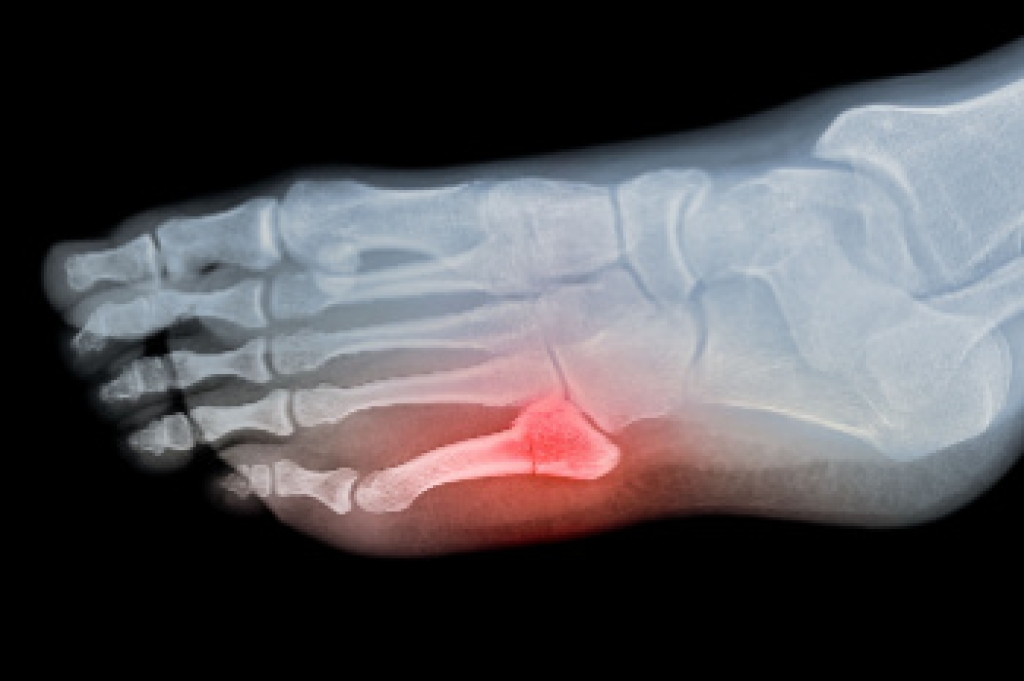

Podiatrists often perform two tests – blood tests and x-rays – when trying to diagnose bunions, especially in the early stages of development. Blood tests help determine if the foot pain is being caused by something else, such as arthritis, while x-rays provide a clear picture of your bone structure to your provider.

Foot fractures can affect various bones, including the toes, metatarsals, sesamoids, and those in the back of the foot. Foot fractures are usually the result of injuries from falls, twists, or direct impacts. The pain associated with foot fractures can significantly increase when weight is applied, making everyday activities challenging. A podiatrist can provide an expert diagnosis, recommend appropriate treatment depending on the cause, and manage rehabilitation. Diagnosing foot fractures typically requires an X-ray, or may necessitate other imaging tests like CT or MRI scans for complex cases. Treatment depends on the specific bone and type of fracture, generally involving immobilization with a splint, cast, or specialized shoe to protect the foot. Patients may be advised to avoid putting weight on the foot to facilitate healing, which can take several weeks. Once the pain subsides, special exercises may be recommended to restore mobility and strengthen the surrounding muscles. If you have fractured a bone in your foot, it is suggested that you schedule an appointment with a podiatrist for a diagnosis and treatment.

A broken foot is caused by one of the bones in the foot typically breaking when bended, crushed, or stretched beyond its natural capabilities. Usually the location of the fracture indicates how the break occurred, whether it was through an object, fall, or any other type of injury.